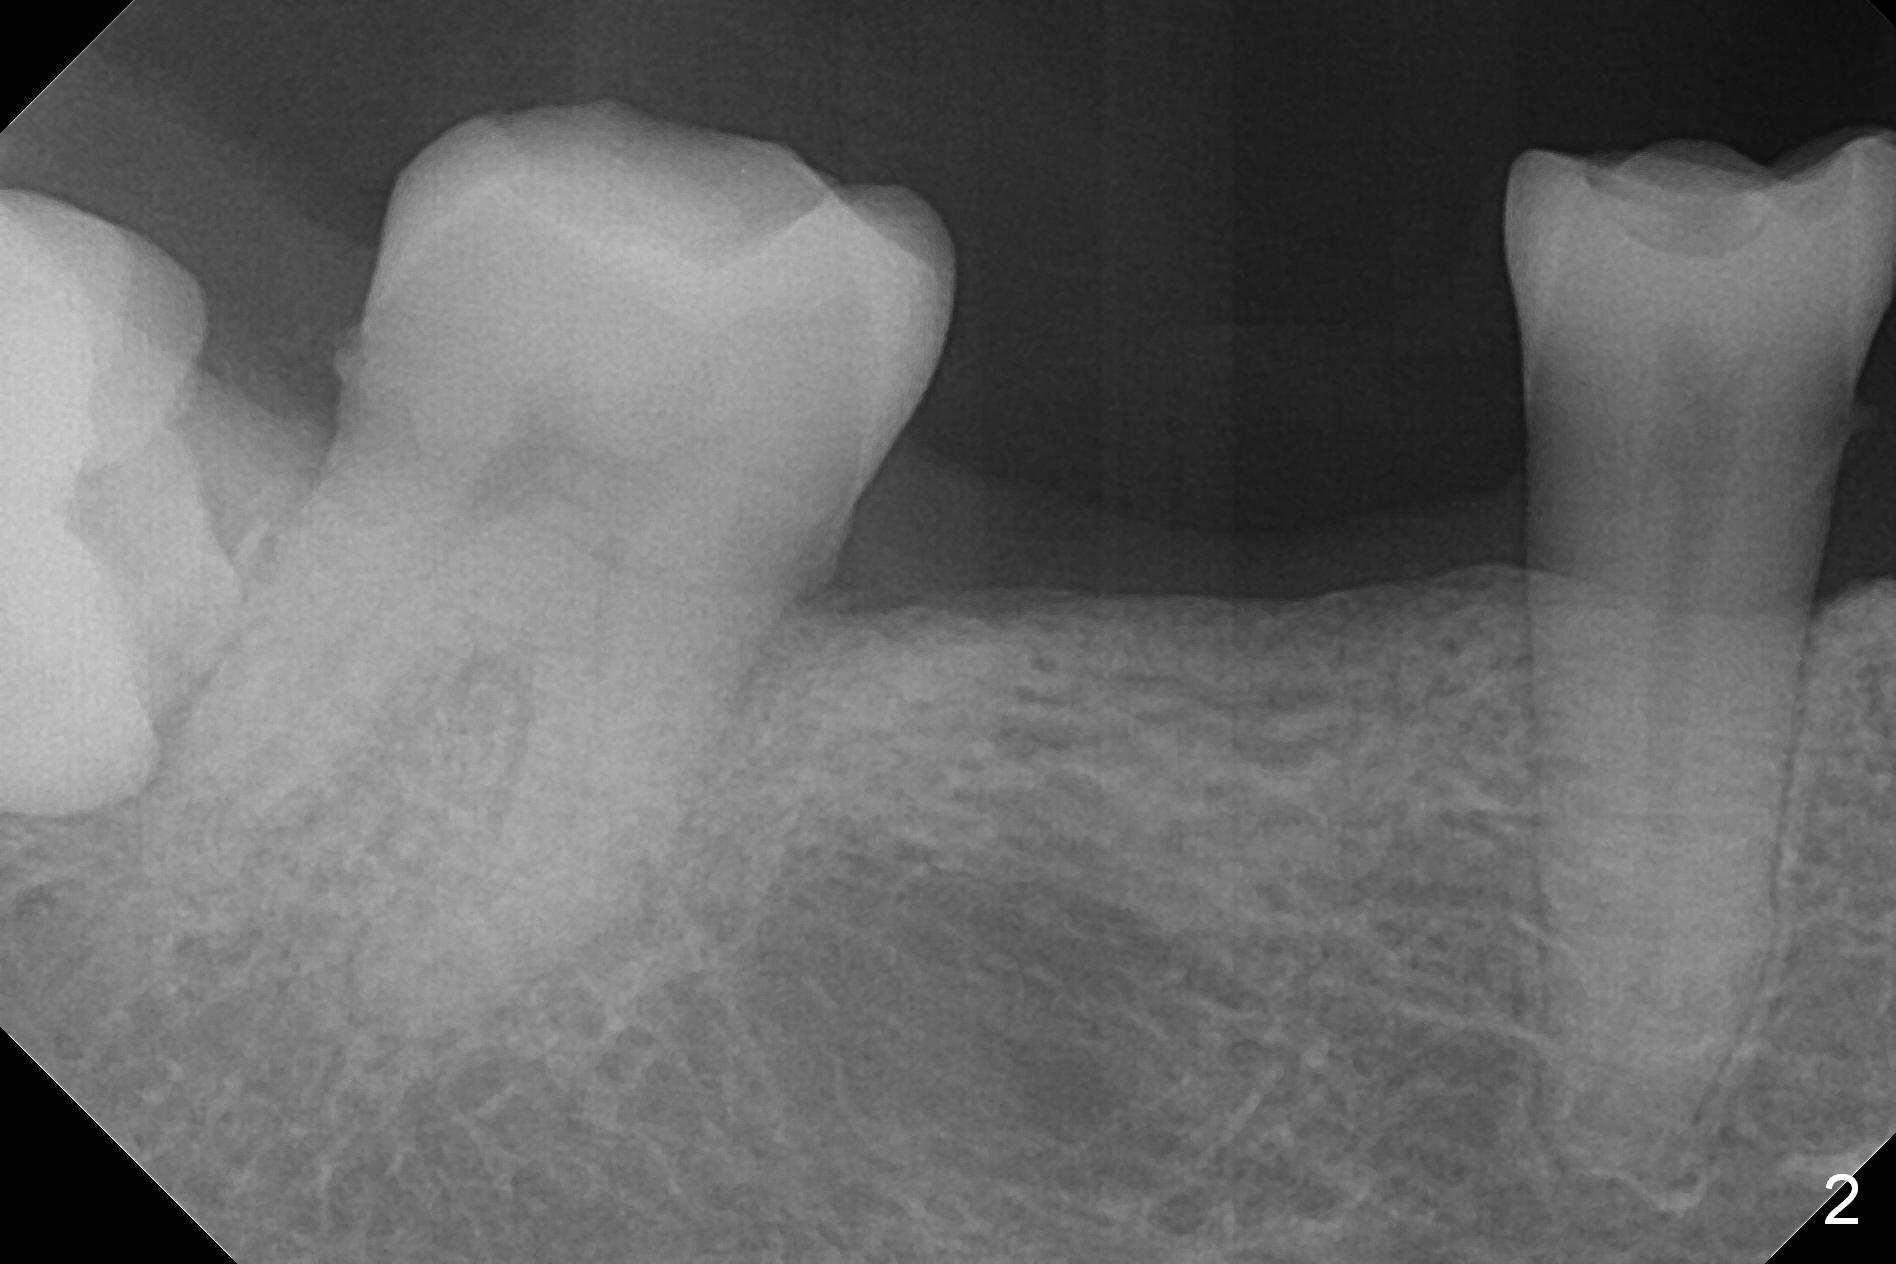

A 57-year-old woman has 3 missing molars, including #30 (Fig.1). Although she looks skinny, clinically the ridge is moderately wide. Magic Split will be used for access (flapless) and bone density testing. From PA, the bone density does not seem to be low (Fig.2). Use the 1.6 mm drill without stopper for further bone density testing. The initial depth will be 15 mm (gingival level, Fig.3). After PA confirmation of the trajectory, use 3.8 mm Magic Drill for 15 mm. Try 4.5x11 mm dummy implant, followed by PA. When an abutment is placed, trim the opposing surpraerupted tooth if necessary (Fig.3 arrow).